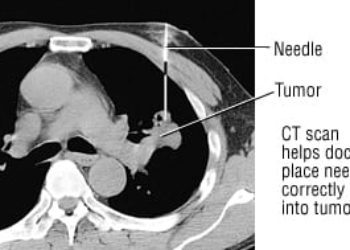

Image: PD